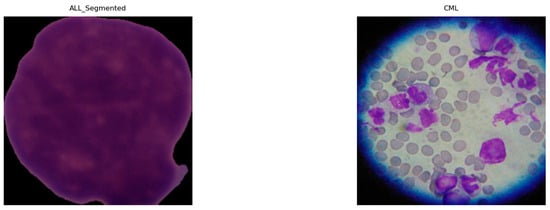

4.5.1. Samples and Visualizations

| 1. | ALL | Microscopic | 15,135 | Cells segmented from 15,135 microscopic images divided into healthy and ALL. | N/A | Kaggle |

| 2. | ALL | PBS | 3256 | Cells segmented from 3256 PBS images divided into two classes: benign and malignant. The ALL group with three subtypes of malignant lymphoblasts: Early Pre-B, Pre-B, and Pro-B ALL. | 100× | Kaggle |

| 5. | CLL | N/A | 113 | Contains 5400 images of 3 types of malignant lymphomas, and 113 images for CLL. | N/A | Kaggle |

| 6. | CML | Microscope | 623 | Contains 623 microscopic images of CML, and the images taken by smartphone camera. | N/A | Raabindata |